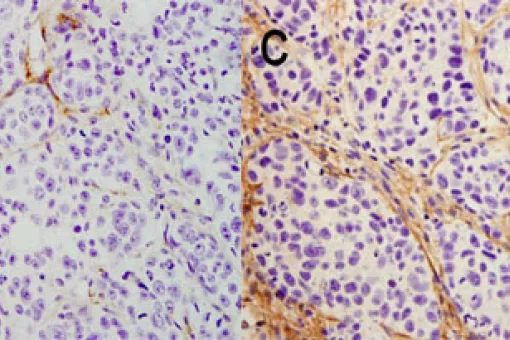

Translational Control of Cell Cycle and Differentiation News